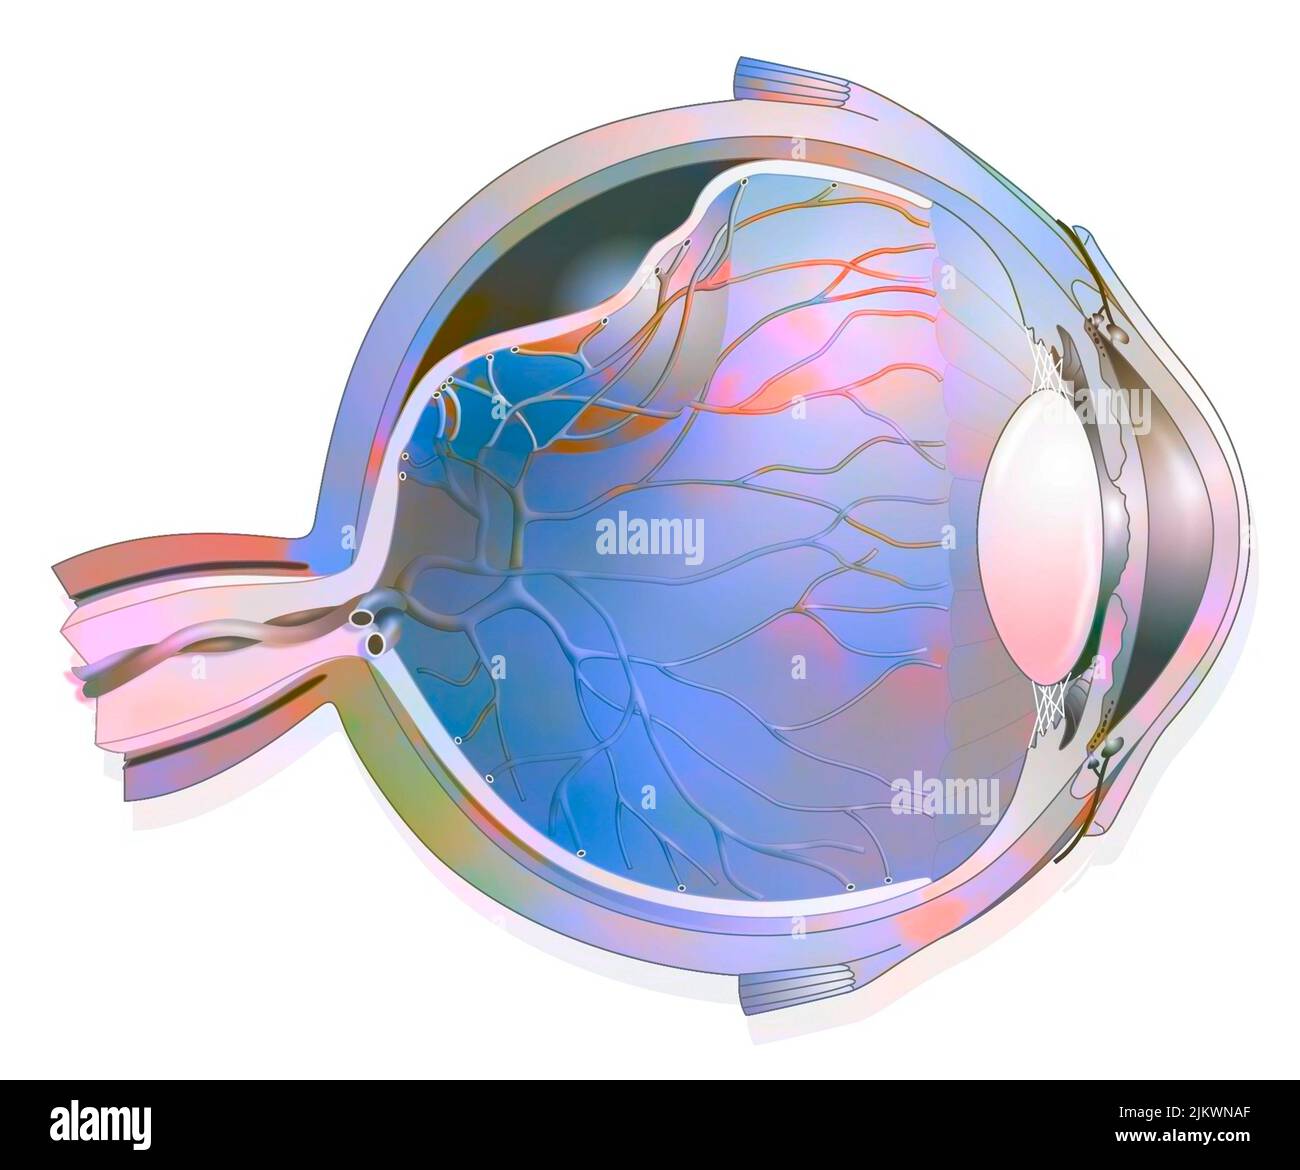

RF2JKWT9A–Oeil, cataracte, phacoémulsification - étape 2: Consiste à casser la lentille avec une sonde.